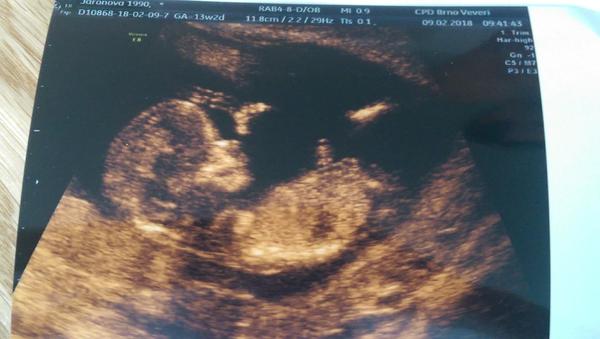

Poznáte pohlaví z fotky?

Ahoj 🙂 momentálně jsem ve 14tt. Ve 12+4tt jsem byla na screeningu v Ústí a zeptala jsem se, jestli jde už poznat nějaké pohlaví. Doktorka se na mě podívala a řekla mi, jestli si to přejeme vědět, ze je to za poplatek s 95% přesností. Tak jsem kývla a doktorka hned řekla, ze podle pohlavního hrbolku to vypadá na holcicku :D ukazala nám, jak by to vypadalo, kdyby to byl kluk a vše nám popsala. Ale já stejně stále přemýšlím a zkoumam fotku...Mimochodem každý kdo na tehle klinice byl, tak jim to pohlaví sdělili a opravdu to tak bylo. Tak co myslíte 🙂)

Já byla taky v Ústí a asi na te dáme klinice... zaplatili jsme 1000 Kč, účet jsme dostali na 900... 😁 sdělili nám, že to vypadá na holčičku. Já si myslím, že je to stejne 50:50

Vidim to na holčičku. Když jsme byli na utz, tak jsem to taky sledovala a hádala holčičku a holčička to byla. 🙂